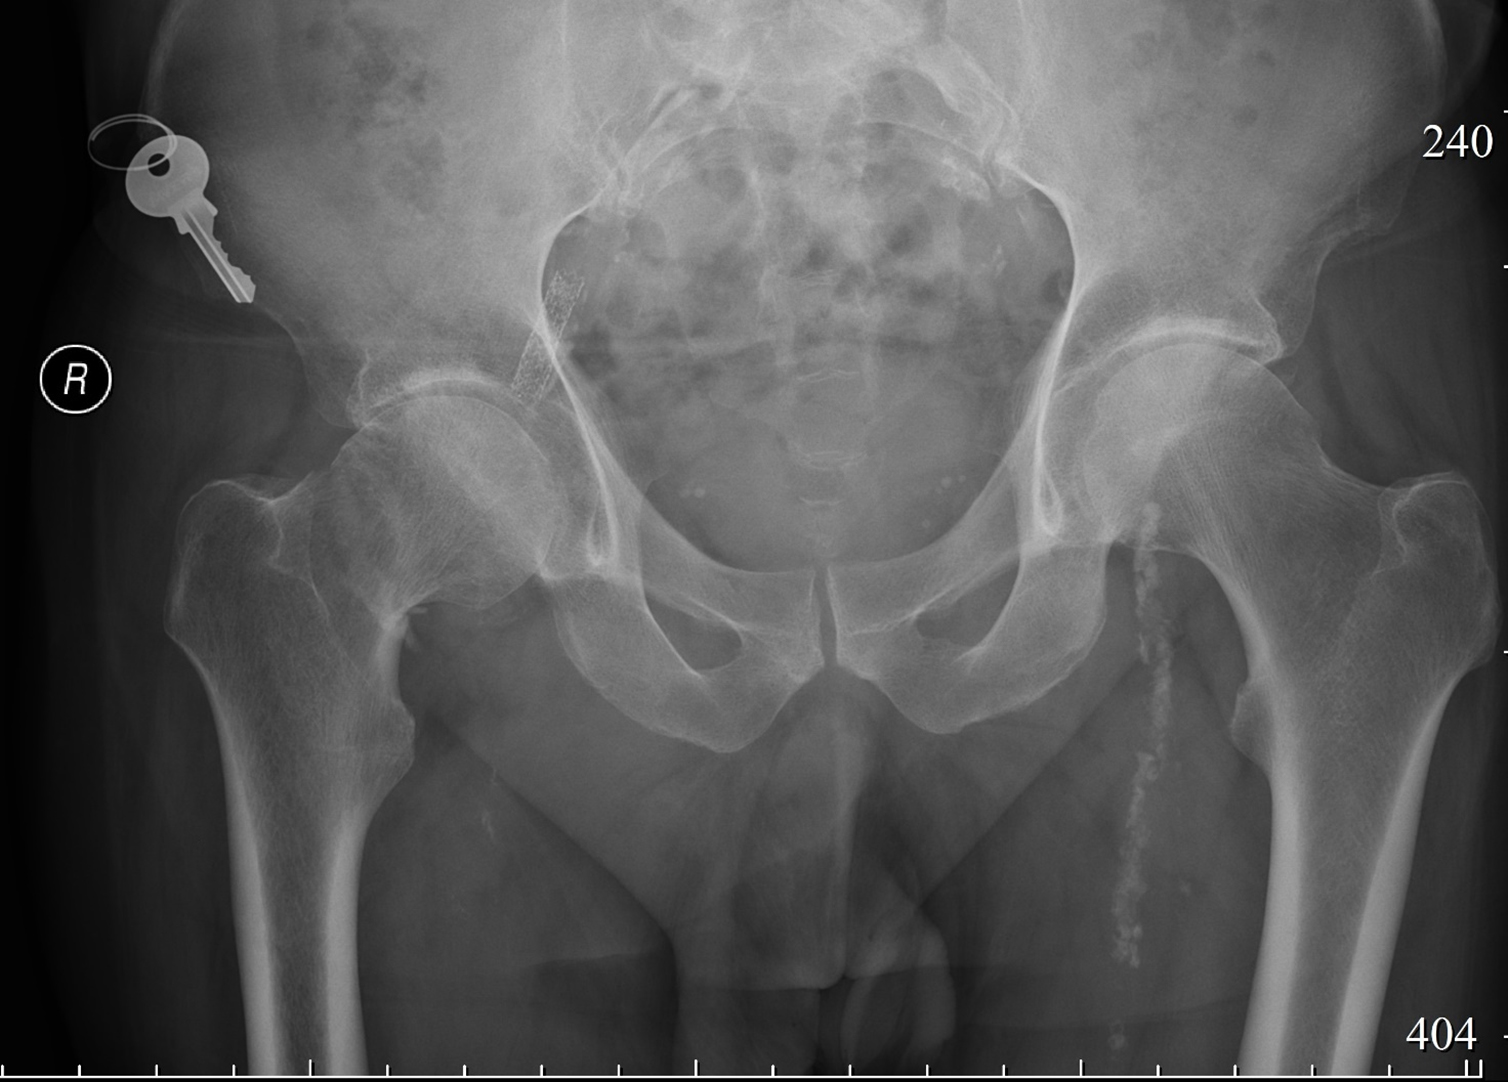

Больной З., 64 года, был доставлен бригадой скорой медицинской помощи в городскую клиническую больницу с жалобами на слабую боль в правом бедре и нарушением функции опоры. Пациент осмотрен травматологом и госпитализирован в травматологическое отделение. В соответствии с анамнезом травма была получена в результате падения на правое бедро. Больной обратился в центральную районную больницу по месту жительства, где ему была выполнена рентгенография правого тазобедренного сустава. На основании полученной рентгенограммы был диагностирован перелом шейки правого бедра со смещением отломков (рисунок 1).

Рисунок 1. Рентгенограмма правого тазобедренного сустава пациента З., сутки после операции.

Figure 1. X-ray of the right hip joint of patient Z., one day after surgery.